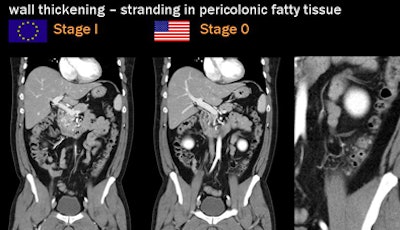

![]() |

| Two staging methods are in widespread use: the Hanson/Stock staging method popular in Europe and the modified Hinchey dominant in the U.S. All images courtesy of Dr. Patrick Rogalla. |

| Diverticular disease above reveals wall thickening and stranding in the pericolonic fatty tissue at CT. Case below shows moderate obstruction and acute inflammation. Both are classified as stage 0 by the Hanson/Stock method and as stage I by the modified Hinchey method. |